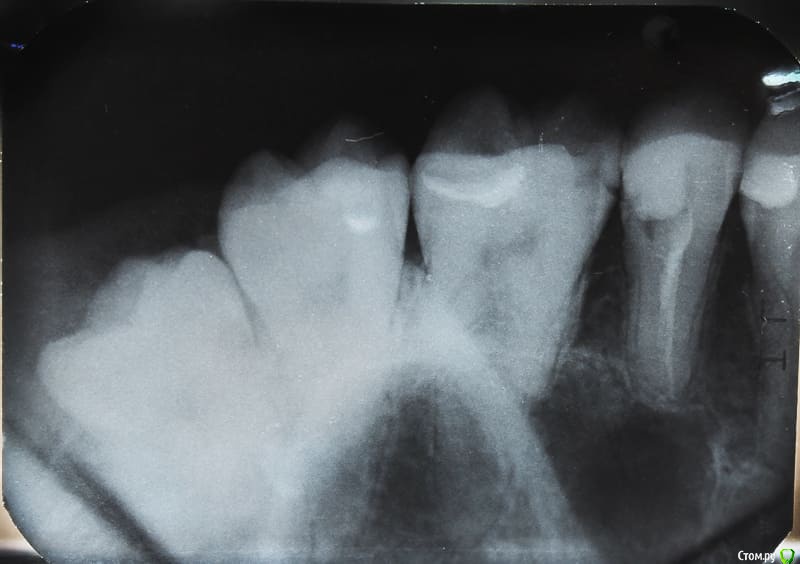

annie23 Опубликовано 11 июня, 2018 Поделиться Опубликовано 11 июня, 2018 Добрый день! Нужна ваша консультация. В январе этого года пролечила пульпит 15 зуба. В какой-то момент он начал реагировать на холодное/горячее, сейчас такого не наблюдается. Изредка где-то далеко чувствую тянущую боль (но это скорее я придираюсь). Что беспокоит на данный момент: 1. Кажется, что внутри забыли что-то инородное (как будто много пломбировочного материала наложили). Один из стоматологов чуть-чуть прошлифовал пломбу, но это ощущение все равно сохраняется.2. Запах от зуба. Он, простите, зловонный (точно такой же как до лечения), особенно это ощущается после чистки зубной нитью. Снимков до пломбировки канала нет, лечила в государственной. После была у двух частных стоматологов, оба развели руками и сказали, что все нормально. Скажите, с этим нужно научиться жить или с этим можно что-то сделать?! (И еще у меня были подозрения на кисту, но никто об этом не упомянул) Ссылка на комментарий

red_butler Опубликовано 11 июня, 2018 Поделиться Опубликовано 11 июня, 2018 Пятый, перелечить корневые каналы и протезировать искусственной коронкой, на шестом лечить кариес на боковой поверхности. 1 1 Ссылка на комментарий

St. Опубликовано 11 июня, 2018 Поделиться Опубликовано 11 июня, 2018 По снимку от зуба осталось не так много и есть большой риск сломать его в будущем. Коронка защитит от этого Ссылка на комментарий